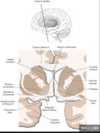

Key gyri on the lateral surface of the frontal lobe

Superior frontal gyrus

Middle frontal gyrus

Inferior frontal gyrus (pars triangularis, pars orbitalis, pars opercularis)

Precentral gyrus

Key sulci on lateral surface of frontal lobe

Superior frontal sulcus

Inferior frontal sulcus

Pre-central sulcus

Key gyri on superior view of frontal cortex

Inferior frontal gyrus

Key sulci on superior view of frontal lobe

Precentral sulcus

Key gyri on medial view of frontal lobe

Paracentral lobule

Cingulate gyrus

Key sulci on medial surface of frontal lobe

Cingulate sulcus

Key gyri on orbital view of frontal lobe

Gyrus rectus

Medial orbital gyrus

Anterior orbital gyrus

Posterior orbital gyrus

Lateral orbital gyrus

Key sulci on orbital surface of frontal lobe

Olfactory sulcus

Orbital sulcus